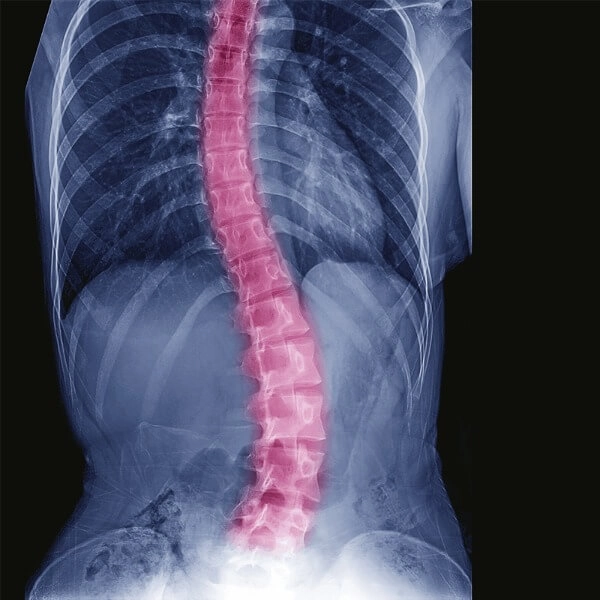

The patient presented with a history of hereditary motor neuropathy with resulting rigid kyphoscoliosis. He complained of breathlessness, difficulty walking, and feelings of depression due to his condition. His back was visibly crooked with a hunchback. The spine displayed gross deformity with a kyphotic degree of 75 and scoliotic degree of 70.

Spinal deformities are reported in some patients with hereditary motor neuropathy such as scoliosis, kyphosis, or kyphoscoliosis. The normal spine has a natural curvature and three segments. The cervical section (neck) and the lower back curvature are ‘c-shaped’ and called lordosis. The portion of the spinal cord in the chest (thoracic spine) is ‘reverse c-shaped’ and is called kyphosis.

Scoliosis is an abnormal curvature of the spine in a sideways direction while kyphosis is an abnormal curvature of the thoracic spine beyond the normal 20-40 degrees, which causes the upper back to appear more rounded and prominent than usual. When both these conditions co-exist, it is known as kyphoscoliosis.